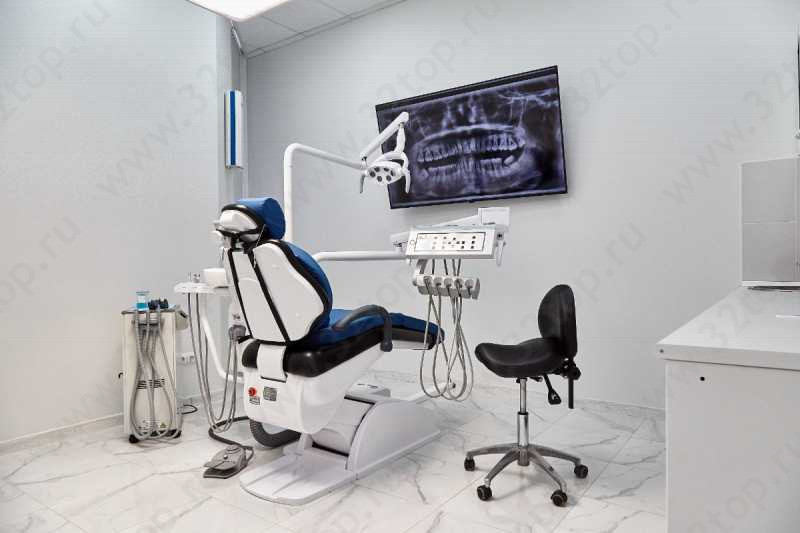

Есть компьютерный томограф

Есть рентген

Фотографии клиники

(28)